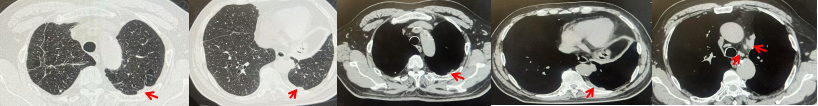

2024.09.12复查胸部CT示左侧胸膜结节,大者约为27mmx13mm,考虑转移可能性大,纵隔淋巴结增大,恶性?(如图6)。患者行胸膜穿刺活检取病理,结果示(胸膜)结合免疫组化,支持鳞状细胞癌,PD-L1(克隆号28-8)TPS约20%。分期为rT0N2bM1a IVA期,DFS为10个月。2024.09.24起行替雷利珠单抗联合紫杉醇+卡铂方案治疗4周期,复查胸CT评效SD(如图7)。后患者因脑梗塞停止治疗,于综合医院就诊,后未返院复查及治疗。

图7:替雷利珠单抗联合白蛋白紫杉醇+卡铂治疗4周期后(2024.12)胸部CT肺窗及纵隔窗